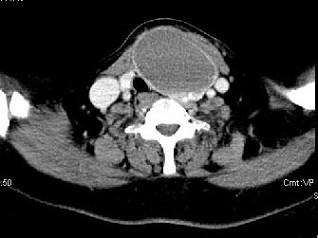

问题 女,56岁 ,发现颈部肿块一月余,CT如图所示,最可能诊断为 ( )

选项 A、甲状腺腺瘤 B、甲状腺脓肿 C、甲状腺乳头状癌 D、甲状腺原发淋巴瘤 E、甲状舌管囊肿

答案 A